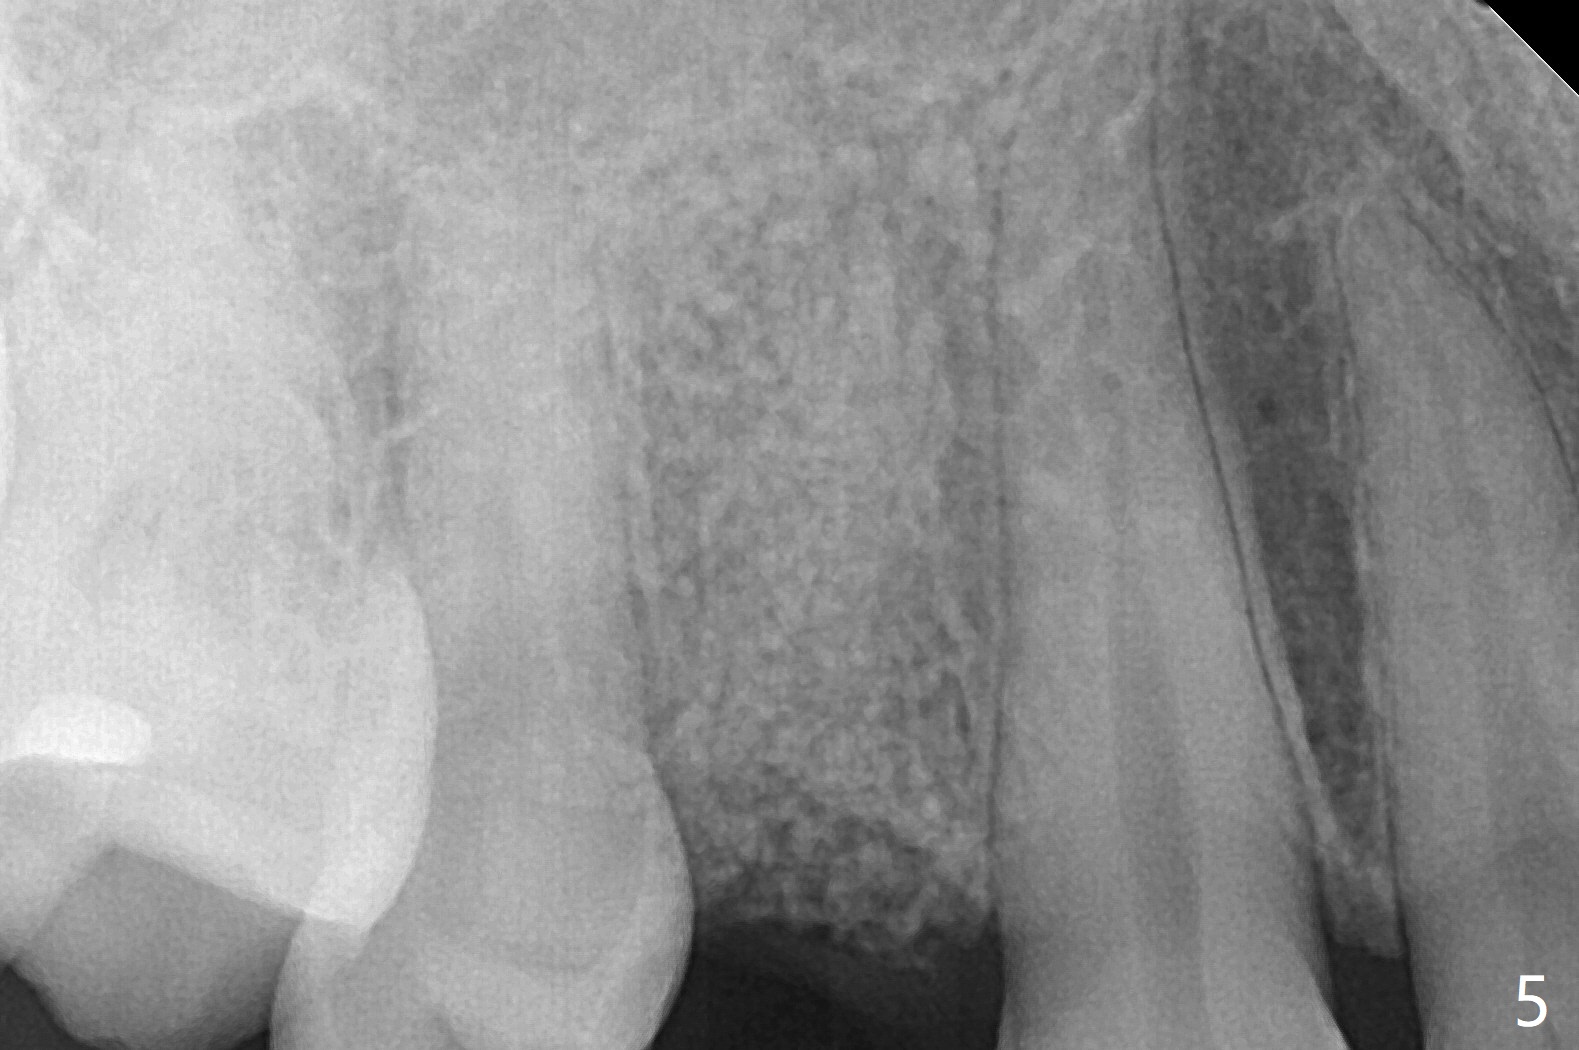

今天临床实践让我对植骨概念和操作有两方面突破,与大家分享讨论。PRF/sticky bone(粘性骨粉)以及血小板因子(成品)对软硬组织缺损修复重建无疑起到不可缺少作用。但是大多数拔牙病例并不是那么严重,放置骨粉和覆盖胶原膜足够了。为了避免费时的缝线固定胶原膜,介绍一种简易固定方法,助手可以做。31岁女不想保留严重龋坏右上4(图一至四,拍摄临床照片,与后期比较,但愿简易植骨不产生骨板塌陷),虽然术前根尖片显示根尖阴影(图四),术中没有根尖骨板缺失。估计没有严重骨板缺损,她又年轻,再生能力强,所以做简易植骨(异体骨,图五),也就是不需要PRF或者血小板因子,骨粉表面放置GEM CAP(9-12月吸收膜),由胶水固定(图六),在放置牙周敷料前,在胶原膜表面涂一层含有抗单纯疱疹病毒凡士林(图七),但愿敷料脱落时,不至于把胶原膜带下来。术后第六天,病人由于左上第二磨牙不适回来,说敷料脱落,没有不适,要求检查,其实膜也丢失(图八,九),骨粉好像挺稳定,没有做如何处理,尽管少量骨粉离开牙槽窝(<)。